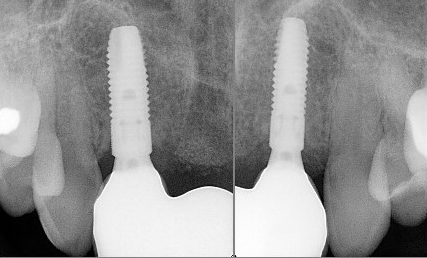

Implant Overdenture (full arch)

Implant Fixed Prosthesis (full arch)

- Implant overdenture:: Designed to replace a full arch of teeth, often used for patients who have lost most or all their teeth.

- Implant fixed prosthesis: A permanent solution for a full arch of lost teeth, providing complete restoration.